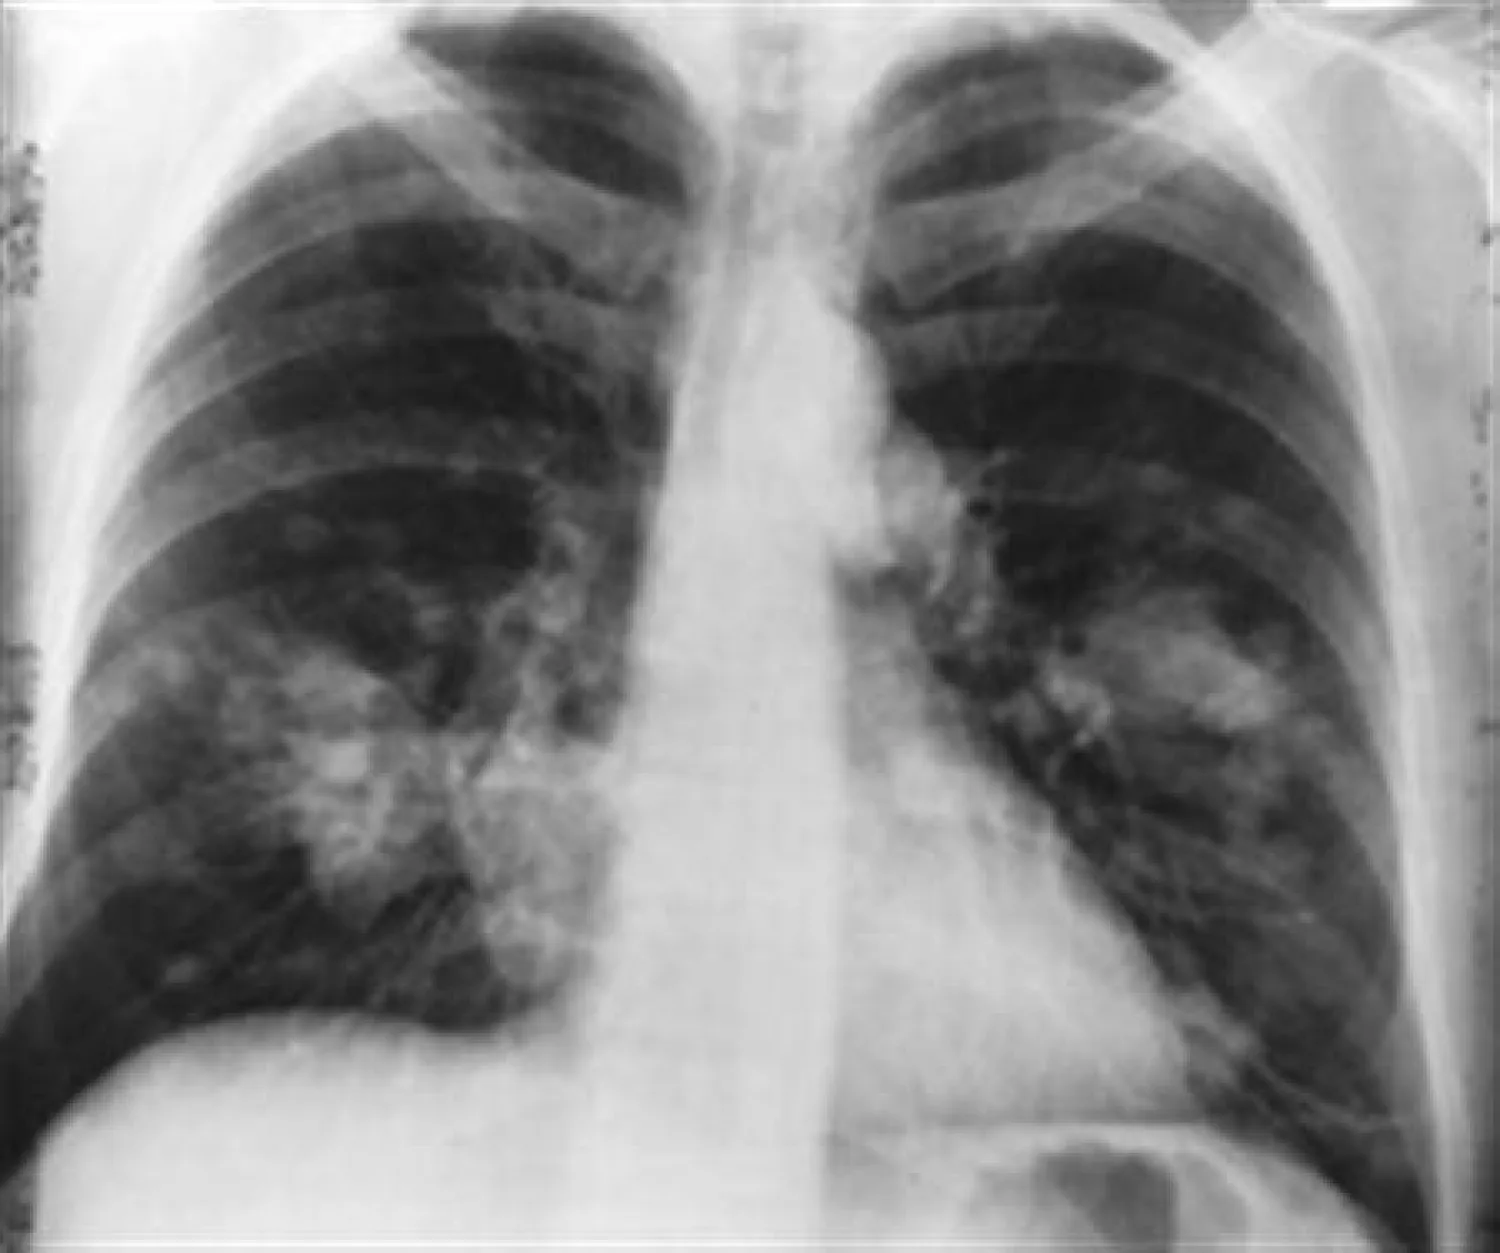

وبالرغم من أن محاولات تطوير علاجات دوائية جديدة تعتمد على وظيفة البروتين p53 لم تنجح إلى حد كبير، إلّا ان نتائج الباحثين تشير إلى أن الوقاية من السرطان قد تكون مجرد أثر جانبي للدور الحقيقي لـ p53 كمنظم رئيسي لإصلاح الأنسجة. وفي هذا الاطار، درس كايزر وأتاردي وزملاؤهما الفئران المختبرية المصممة هندسيًا لتطوير سرطانات الرئة الشبيهة جدًا بالنوع الأكثر شيوعًا من سرطان الرئة لدى البشر. ويُعد هذا النوع من سرطان الرئة، المسمى بسرطان الرئة الغدي، السبب الرئيسي لوفيات السرطان في جميع أنحاء العالم؛ فحوالى نصف الأورام الغدية في الرئة لها طفرات في p53؛ وغالبًا ما يعاني الأشخاص المصابون بهذه السرطانات من سوء التشخيص.

تنشأ الأورام السرطانية الرئوية من نوع من الخلايا يسمى AT2 تقع في الأكياس الدقيقة التي تتبادل الأكسجين لثاني أكسيد الكربون في الرئة. فتفرز خلايا AT2 المواد الخافضة للتوتر السطحي التي تمنع الكيس من الانهيار، نوعا آخر من الخلايا في الأكياس يسمى خلايا AT1 يسهل تبادل الغازات الذي يبقينا على قيد الحياة مع كل نفس. وعندما تتلف أكياس الرئة، مثل التعرض للمواد الكيميائية، تنقسم خلايا AT2 لإنتاج المزيد من خلايا AT2. فتنتقل بعض خلايا AT2 أيضًا أو تتمايز إلى خلايا AT1 لإصلاح الضرر.